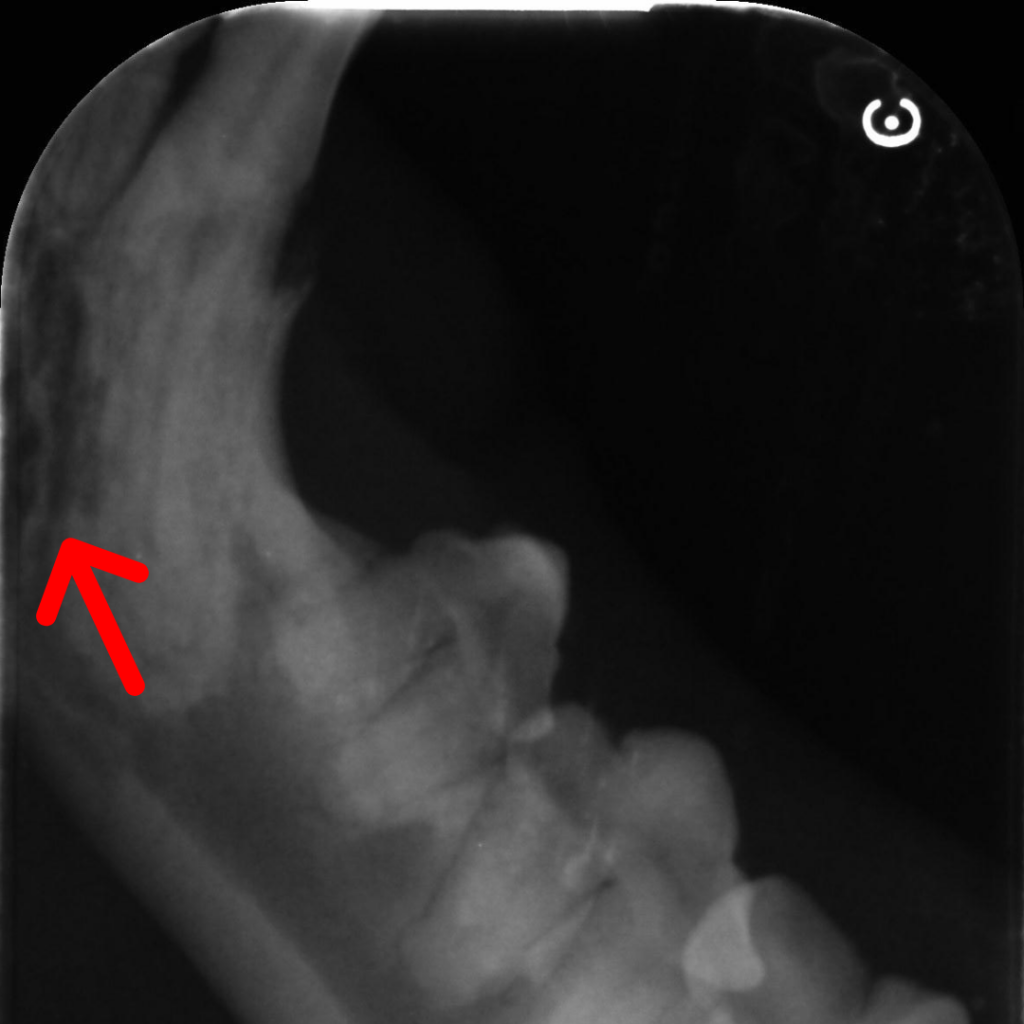

It can be difficult to diagnose without dental X-rays as animals hide their pain. Very rarely, we will have an owner notice that their pet is only eating on one side of their mouth, or has stopped eating dry food, or has started dropping more food than usual. Sometimes they notice a jaw “shudder”, or their pet drools more than usual. But most of the time, because our animals are so good at hiding pain, these lesions aren’t picked up until your pet is examined at the vet. If there is a lesion above the gum line, we can sometimes see it as a red exposed spot on your pet’s teeth. Other times we can see a “pit” in the enamel that is painful to touch and that our probes catch in.

Still other times, we notice gingivitis or periodontal disease and recommend a dental. It isn’t until we are taking dental X-rays of your pets mouth that we pick up that there may be resorptive lesions, as the entire lesion can occur under the gumline.

Often when the lesion is under the gum, the tooth becomes replaced with bone, and the X-rays no longer show the normal periodontal ligament around the tooth. Instead the tooth root blends into the bone around it (see Green Arrows for normal periodontal ligaments.)

Type 1 lesions are focal, and usually above the gumline. In these cases the tooth root is usually intact, and on Xray you can see teh normal black line around the tooth root (which is the periodontal ligament). This type is most commonly associated with inflammation and gum disease.